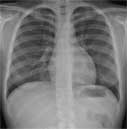

Posteroanterior chest on a normal female.